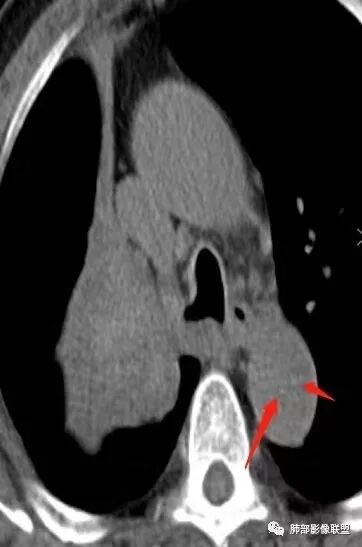

影像:影像右侧大支气管阻塞,临床没有症状或很轻微,要想到胃腺癌转移;胸壁代偿好,透亮度稍低不明显,慢性过程;34.8-52.5HU,主病灶支气管前壁另有1结节,都做成增强两期了,动脉期较平扫有强化;

降主动脉内也有啊

先转移到支气管壁上淋巴管

然后突破粘膜

本质上还是血行淋巴转移